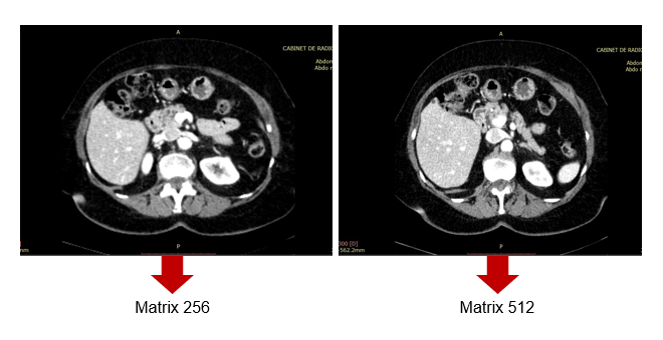

SR and Matrix Size

As for matrix size, 512-by-512 has been used in conventional CT, but larger matrix sizes, such as 1024-by-1024 and 2048-by-2048, are available with Ultra high-resolution CT (U-HRCT).

According to a new study recently published in Academic Radiology, in ultra-high-resolution computed tomography (U-HRCT) scans, a large matrix size maintains the spatial resolution and improves the image quality and assessment of lung diseases when compared to a 512-matrix size.